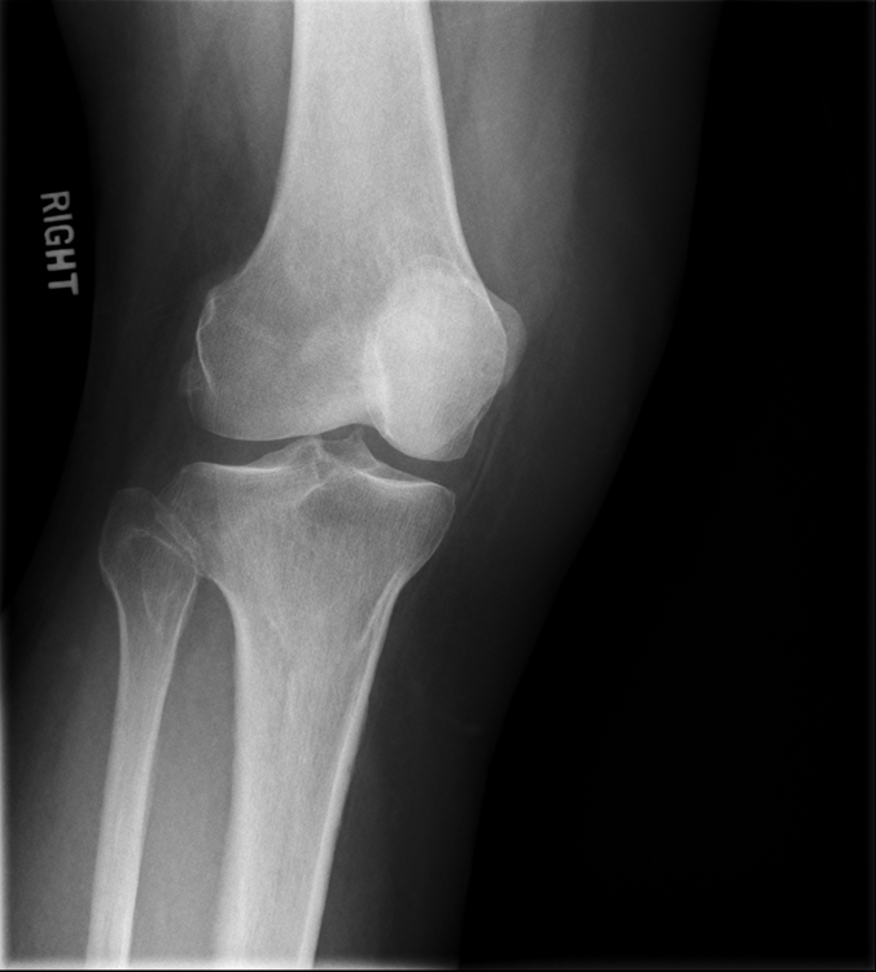

osteoarthritis (degenerative joint disease)

generalized disorder pathologically characterized by loss of joint cartilage & reactive new bone formation

traumatic, stress to joint

what is the casue of osteoarthritis?

advance stage → subtractive disease

pt w/ osteoarthritis

what is this image?